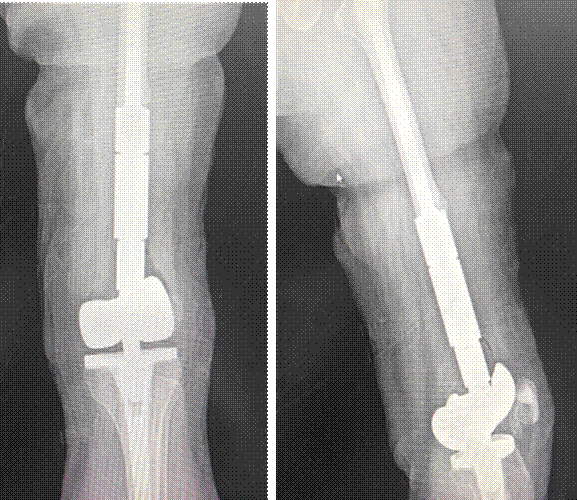

患者董女士(32岁)两年前因左股骨皮质旁骨肉瘤行保肢手术,术后四年影像学提示肿瘤复发。由于瘤体巨大,外院大多建议行截肢手术。

患者抱着一丝希望,慕名到同济大学附属同济医院骨科副主任袁锋专家门诊就诊。在完善术前检查后发现,患者股动脉及股静脉嵌顿于肿瘤缝隙之中。鉴于患者保肢欲望强烈,袁锋带领蔡涛等相关团队术中经过仔细操作,在完整切除肿瘤的前提下,成功分离出肿瘤缝隙中的股动脉及股静脉,为患者进行了铰链式膝关节假体置换,成功完成了患者的保肢手术。

术前影像学

术后影像学